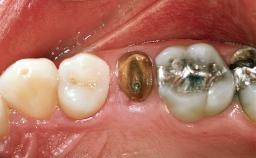

A 55-year-old female patient was referred for consultation and treatment. Her chief complaint was pain associated with the mandibular right second premolar (tooth 45). The patient denied systemic or oral diseases capable of compromising dental care. She had a history of adult periodontitis, for which she continued to be treated. Her response to therapy and motivation towards dental health were considered excellent. Intraoral examination revealed a cantilever fixed dental prosthesis in the mandibular right quadrant, with retainers on teeth 45 and 47,and pontics at sites 44 and 46.The retainer on tooth 45 was loose, and the tooth was carious. Radiographic evaluation confirmed the extent of the caries and the maintenance of bone around tooth 45 and in the pontic region 46.